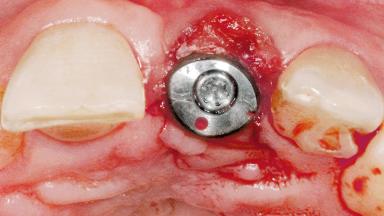

Late Flapless Placement of an Implant in a Maxillary Left Central Incisor Site

A 39-year-old male patient presented with a chief complaint of discomfort and gingival discoloration around his maxillary left central incisor. He was in good general health and was a non-smoker. His past dental history was significant because of the traumatic fracture of tooth 21 in a sporting accident at age 13. Initial dental treatment included endodontic therapy and a full-coverage restoration. The patient became symptomatic 5 years later, when structural failure of the tooth resulted in the dislodgment of the crown. Endodontic retreatment, apical surgery, and post-and-core restoration were performed.

Type of Implants One-Piece

Bone Augmentation Horizontal|Staged

Augmentation Materials Xenogenous|Membrane

Soft Tissue Grafting Simultaneous

Bone Volume Deficient horizontally, requiring prior grafting